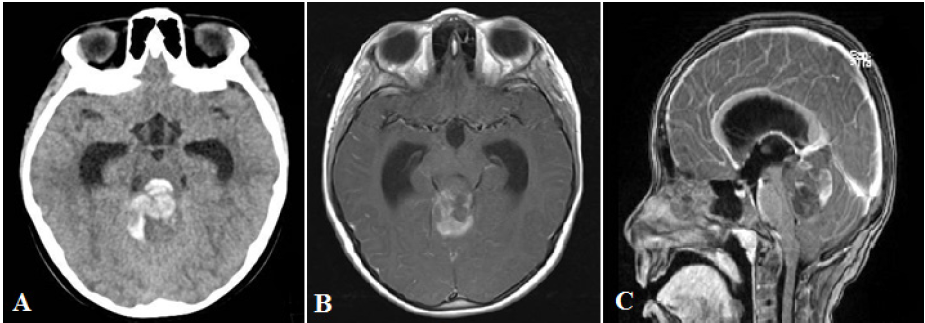

Paciente mujer de 6 años ingresó al servicio de emergencia en diciembre del 2020 por presentar dos días antes del ingreso cefalea y malestar general. El día del ingreso, la paciente presentó dolor abdominal con náuseas y vómitos a repetición. Al examen físico, la paciente presentaba un puntaje en la ECG de 13, respondía órdenes simples verbales, estaba pálida, con mucosas secas, ojos hundidos y un llenado capilar de dos segundos. El abdomen estaba blando, con leve dolor difuso a la palpación profunda. Se realizó una tomografía de abdomen donde se observó el apéndice cecal con ausencia de contenido de aire y leve incremento de la densidad de su grasa a nivel distal, con sospecha de apendicitis. Sin embargo, la paciente presentó también deterioro progresivo del sensorio estando en el servicio de emergencia indicándose tomografía cerebral sin contraste donde se evidenció hidrocefalia obstructiva debido a un proceso expansivo de fosa posterior de densidad heterogénea, con componente hemorrágico (figura 3A). Se realizó drenaje ventricular externo de emergencia a nivel frontal derecho obteniéndose líquido cefalorraquídeo a presión incrementada. La paciente pasó a la Unidad de Cuidados Intensivos Pediátricos. Se indicó una resonancia magnética cerebral donde se observó un proceso expansivo infratentorial de componente sólido y quístico, con sangrado asociado, captador de contraste, ubicado en vermis cerebeloso con extensión a pedúnculos y hemisferios cerebelosos adyacentes con compresión del acueducto de Silvio y el cuarto ventrículo (figura 3B y 3C).

Tras la resonancia magnética, la paciente cursó con bradicardia sostenida, indicándose intervención quirúrgica que consistió en craneotomía suboccipital con abordaje paravermiano derecho y resección de tumor, el cual era de color grisáceo, vascularizado, con plano de clivaje parcialmente definido. Se realizó una resección quirúrgica amplia de la lesión tumoral, sin complicaciones intraoperatorias. La paciente evolucionó favorablemente tras intervención quirúrgica recuperando completamente el estado del sensorio. Se operó nuevamente para retirar el drenaje ventricular externo y colocar un sistema de derivación ventriculoperitoneal de presión media contoured pediátrico; no hubo complicaciones perioperatorias. La muestra quirúrgica fue informada como sarcoma fusocelular intracraneal de alto grado con la siguiente inmunohistoquímica: pérdida de la expresión nuclear del ATRX, expresión nuclear focal del MyoD1, P53 positivo intenso y difuso nuclear, ki-67 80%. Tras el diagnóstico histológico, se activó el seguro oncológico particular del paciente siendo transferida a otra institución privada a pedido de la familia para recibir quimioterapia y radioterapia.

A: corte axial de tomografía cerebral sin contraste muestra sangrado a nivel de cuarto ventrículo con dilatación de cuernos temporales de los ventrículos laterales. B: corte axial de resonancia magnética cerebral con contraste evidencia proceso expansivo de fosa posterior con captación heterogénea de contraste. C: corte sagital de resonancia magnética cerebral con contraste muestra proceso expansivo dependiendo de vermis cerebeloso que produce severa compresión del cuarto ventrículo y dilatación del sistema ventricular.